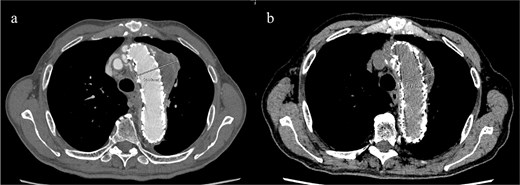

CT revealed no endoleak, but the aneurysm had enlarged to a diameter of 56 mm (Fig. 1b). Three-dimensional CT revealed straightening and proximal migration of the FET (Fig. 2). No clear signs of pulmonary parenchymal hemorrhage or findings suggestive of the mass were reported. Laboratory tests indicated mild anemia, with a hemoglobin of 9.7 g/dL and hematocrit of 29.0%. No infectious or inflammatory diseases that could cause hemoptysis were identified.

(a) Three-dimensional CT image 1 year after total arch replacement with a FET. (b) Three-dimensional CT image 2 years after total arch replacement with a FET demonstrating straightening and migration of the FET.